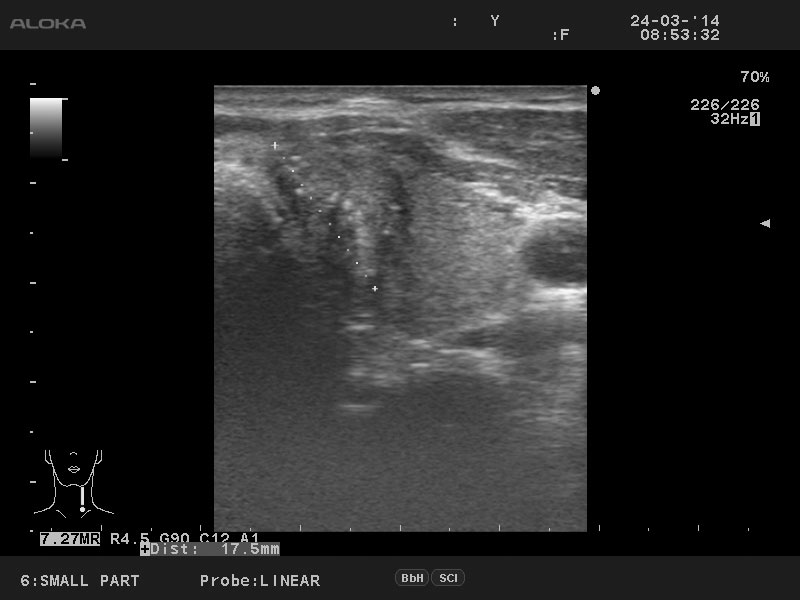

Мужчина 50 лет, жалоб нет.

3.jpg

Диагноз доказан цитологически.